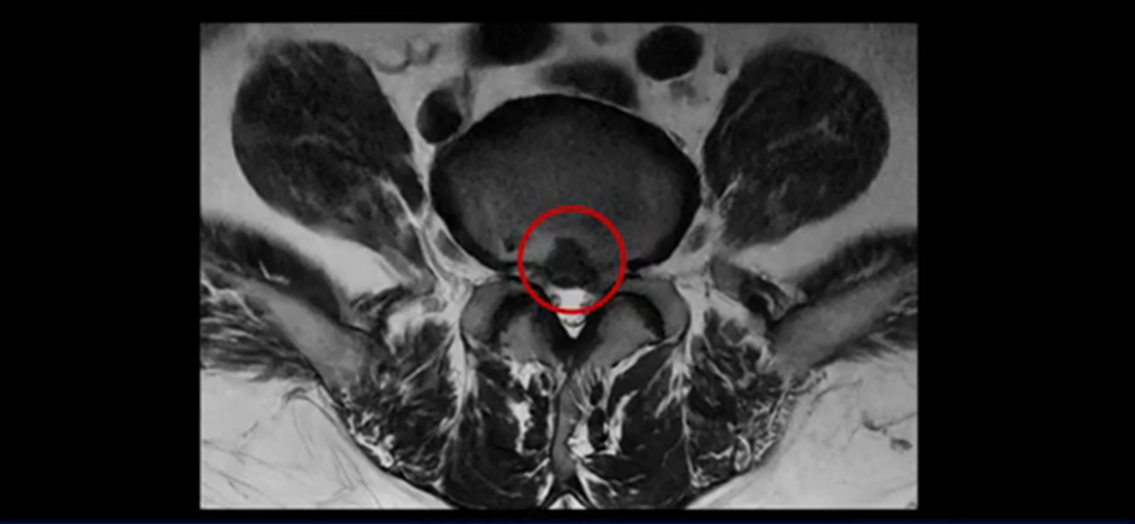

이분 MRI를 잠깐 보실까요? 보시면 두 마디가 특히 안 좋은데 3번 4번 디스크가 터져서 흘러 내려 있습니다.

보시다시피 흘러 내려온 디스크 수핵이 신경 공간의 왼쪽으로 보입니다.

그런데 이분은 4번 5번에도 디스크 파열이 있습니다.

가운데로 심하게 밀려 나와 있는데요.

또 4번 5번에는 협착으로 척추관이 많이 좁아져 있습니다.

또 왼쪽 신경 가지들이 빠져 나가는 신경구멍들이 여러 마디가 좁아져 있습니다.

이런 이유들 때문에 왼쪽 엉덩이부터 종아리, 발가락까지 저리고 아픈 겁니다. 그래서 서둘러 병원에 가셨는데요. 그래서 서둘러 병원에 가셨는데요. 여러분이 꼭 아셔야 할 게 이렇게 다리가 심하게 저리고 아프면 X-ray만 찍을 게 아니고 MRI를 찍어 보시는 게 맞습니다. X-ray로는 디스크가 터졌는지 신경구멍이 좁아진 협착이 있는지를 정확히 할 수가 없습니다. 그래서 이분은 당장 아픈데 해결이 안 되니까 제주도에서 유명하다는 한의원으로 갔습니다.